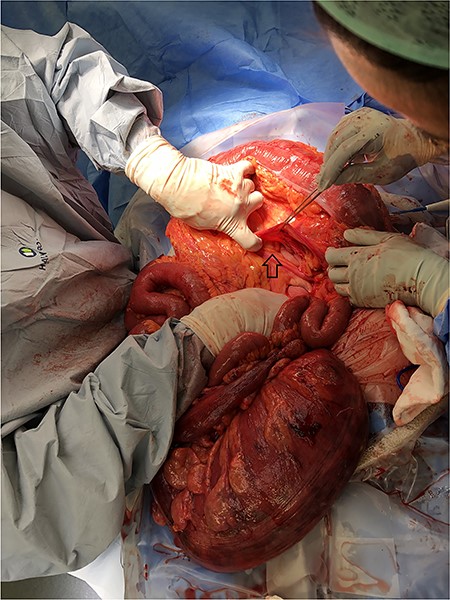

A 93-year-old patient who has history of recurrent sigmoid volvulus presented with a week of abdominal distension and bowels not working. Initial blood test revealed that she has white cell count 11.3 × 109/L, CRP 12 and lactate of 1.9. CT abdomen was performed on admission showed features of sigmoid volvulus. Patient was booked for flexible sigmoidoscopy to decompress the sigmoid volvulus. Flexible sigmoidoscopy revealed that there was significant mucosal necrosis of the sigmoid colon. A diagnostic laparoscopy was performed to determine the severity of necrosis. Laparoscopy reported that the sigmoid colon was oedematous but no signs of transmural necrosis. Patient was kept in the hospital for observation but there were no signs of improvement. Day 4 of the admission, patient continues to deteriorate clinically and had a medical emergency team response call for worsening pain and hypotension, and a repeat CT abdomen was performed. The images were consistent with sigmoid volvulus through transmesocolon defect resulting an internal hernia (Figure 5–7). The patient had emergency laparotomy. The sigmoid colon was found to be in the supracolic compartment and required decompression prior to reduction (Figure 1–4). There was transmural necrosis close to the rectosigmoid junction. Patient underwent Hartmann procedure. Patient recovered well postoperatively and discharged to home.

Sigmoid Volvulus pre-decompression within the supracolic compartment.